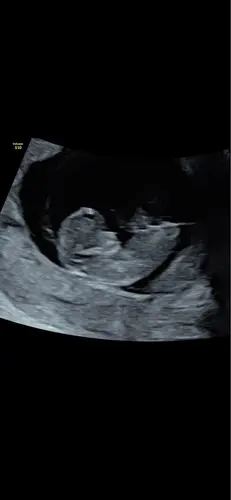

Ik ben 11 weken zwanger. Weten jullie wat het wordt?